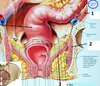

1? 2? 3?

Green arrow?

Red arrow?

Sacral splanchnic nerves - Preganglionic sympathetic fibers (they came down the chain) which will synapse in the inferior hypogastric plexus. They provide sympathetic innervation to the pelvic organs.

4? 5?